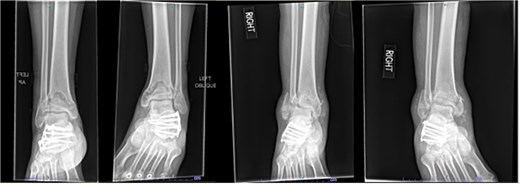

A 57-year-old male with a body mass index (BMI) of 48.7 kg/m2 and multiple comorbidities, including asthma, coronary artery disease, hypertension, hyperlipidemia, ischemic cardiomyopathy, obstructive sleep apnea, and hypothyroidism, following a motor vehicle collision when he lost control of his vehicle due to a coughing spell. His injuries included bilateral pilon fractures (Fig. 1), a T2 superior endplate fracture, and bilateral pulmonary contusions. He initially presented to a regional hospital and was transferred to our facility 10 days after the injury.

Anterior-to-posterior (AP) radiographs of patient 1 obtained 10 days after injury, upon transfer to our facility, demonstrating bilateral pilon fractures.